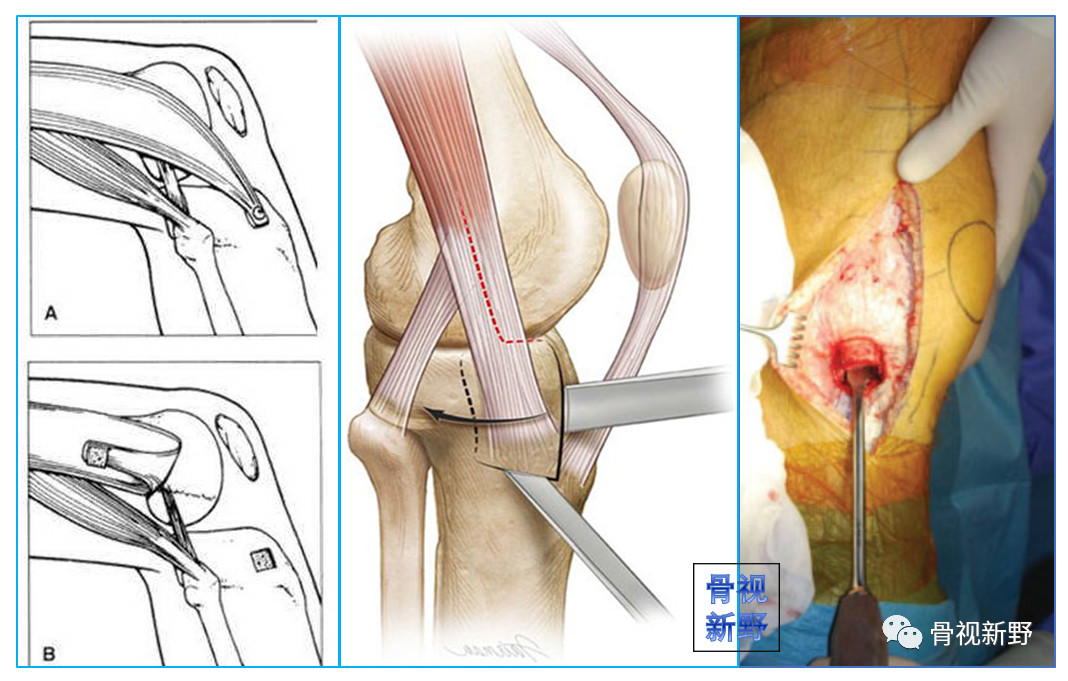

适应症:II型外侧髁Hoffa骨折。操作:自髂胫束和股二头肌之间进入。

改良后外侧入路

适应症:II型外侧髁Hoffa骨折。

操作:自股骨外上髁至腓骨颈做一纵向切口,首先在腓骨颈远侧显露腓总神经,并向近侧游离,切开股二头肌肌腱(前)和腓总神经之间的深筋膜,股二头肌牵向外侧,腓总神经牵向内侧,显露后外侧关节囊,自远侧半月板附着部位向近侧纵向切开关节囊,在半月板位置的关节囊留置缝线,用以牵开关节囊显露股骨远端。

患者仰卧位,自股骨外上髁至腓骨颈做一纵向切口。

切开股二头肌肌腱(前)和腓总神经之间的深筋膜。

显露腓总神经,股二头肌牵向外侧,腓总神经牵向内侧。

复位和临时固定。